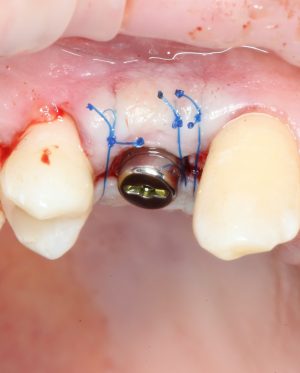

Прежде, чем приступить к аугментации (пластике) лунок зубов, мы подготовили лунки для имплантатов. В таких клинических случаях нет необходимости в использовании шаблона. Вместо этого, мы применяем общепринятые правила позиционирования и соблюдаем рекомендации производителя по хирургическому протоколу:

В процессе ирригации лунки промываются, что позволило нам еще раз подтвердить ранее сделанные выводы. С помощью аналогов имплантатов, входящих в хирургический набор Xive, мы проверили возможность стабилизации имплантатов в будущих лунках. Исходя из правил подбора и позиционирования имплантатов (я очень рекомендую почитать об этом здесь>>) мы остановились на Xive S диаметром 3,4 мм и длиной 13 мм.

Установка имплантатов

По ряду уже упомянутых выше причин, для решения этой клинической задачи мы выбрали имплантаты Xive. Лунки для них мы уже приготовили. возможную первичную стабильность оценили. Имплантаты мы установили с усилием чуть больше 15-20 Нсм — такого крутящего момента более, чем достаточно, особенно если учесть, что временные коронки будут соединяться между собой.

Подробно о том, что такое крутящий момент и хирургический протокол можно прочитать здесь>> и тут>>, соответственно. Из-за использования специальных индивидуализируемых временных абатментов, имеющих только три положения, нам нужно позиционировать платформу имплантатов по граням. Это очень просто  — мы выводим вырез абатмента TempBase (он входит в комплект поставки) вестибулярно.

После перкуторной проверки стабильности имплантатов и точности позиционирования, мы переходим к следующему этапу — сохранению десневого контура.

Установка имплантатов занимает около двух минут.